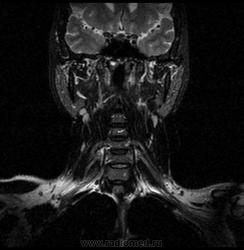

06.06.2011 МРТ - головы и шеи.

Пацентка 36 лет, с жалобами на припухлось в околоушной области справа.

В глубокой доле  правой околоушной железы  на фоне неизмененной паренхимы зона  гетерогенного по Т2, гипоинтенсивного по Т1  с единичными гиперинтенсивными включениями.При контрастировании- накопление контраста диффузное неоднородное и по периферии.Рискну предположить злокачественное образование ( аденокарцинома) с низкой степенью злокачественности( есть капсула, экспансивный рост).Сильно не расстреливайте.

Проблема в том, что перед челюстно-лицевым хирургом стоит распространенность любого объемного процесса, в данном случае все упирается в возмможную травму лицевого нерва и конечно же с дальнейшим его парезом, а ведь женщина  еще молодая. Образование имеет тонкостенную оболочку, по структуре неоднородно, с наличием кальцината, при этом МР-сигнал от окружающих анатомических структур(как костных так и мышечных) не изменен, т.е. об инфильтративном росте речи не идет, в какой то степени доброкачественное. В конкретном случае лицевой нерв с ретромандибулярной веной просто несколько оттеснен.

По гистологии аденома околоушной слюнной железы, но после удаления пока сохраняется парез лицевой мускулатуры, возможно временный.